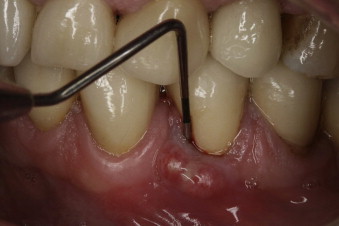

A draining sinus tract appearing next to the tooth that looks like a boil or ulcer, which is often a sign that there is an infection beneath the tooth

A pocket between the gum and the tooth, near the fracture, where the gum essentially detaches from the tooth

A dental professional or specialist (usually an endodontist) may diagnose a fracture during a root canal procedure if they can see a crack. If the fracture occurs after the procedure, they might need to take X-rays, which may show the fractured root characteristically shaped like the letter J, or the specialist may also use a diagnostic method known as transillumination, where they shine a light through your tooth to detect any fracture lines.